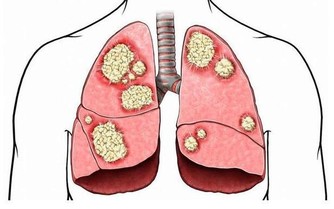

3,烤肉 由於烤肉在熏烤過程中,會產生如 「苯」等有害物質,是誘發癌的因子。